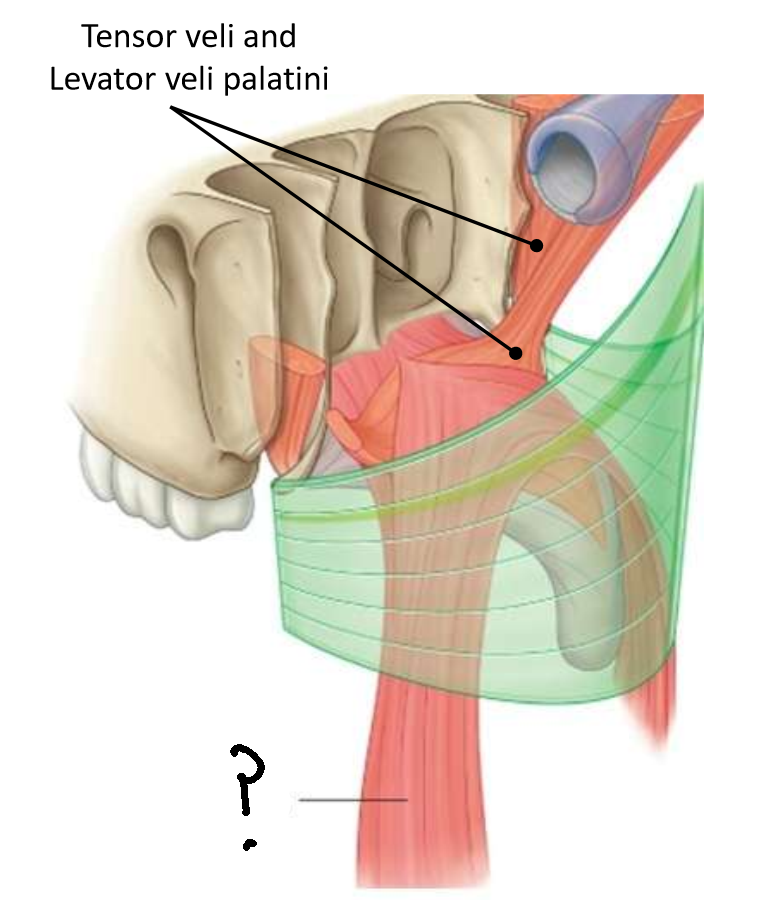

Which muscle is this?

tensor veli palatini

What are the two parts of this muscle?

muscular and fibrous

What is the function of this muscle?

tenses soft palate, opens pharyngotympanic tube

What innervates this muscle?

medial pterygoid nerve of mandibular branch of trigeminal

Which muscle is this?

levator veli palatini

What are the attachments of this muscle?

petrous part of temporal bone and pharyngotympanic tube → palatine aponeurosis

What is the function of this muscle?

lifts soft palate to close nasopharyngeal isthmus

What innervates this muscle?

pharyngeal branch of pharyngeal plexus of vagus nerve